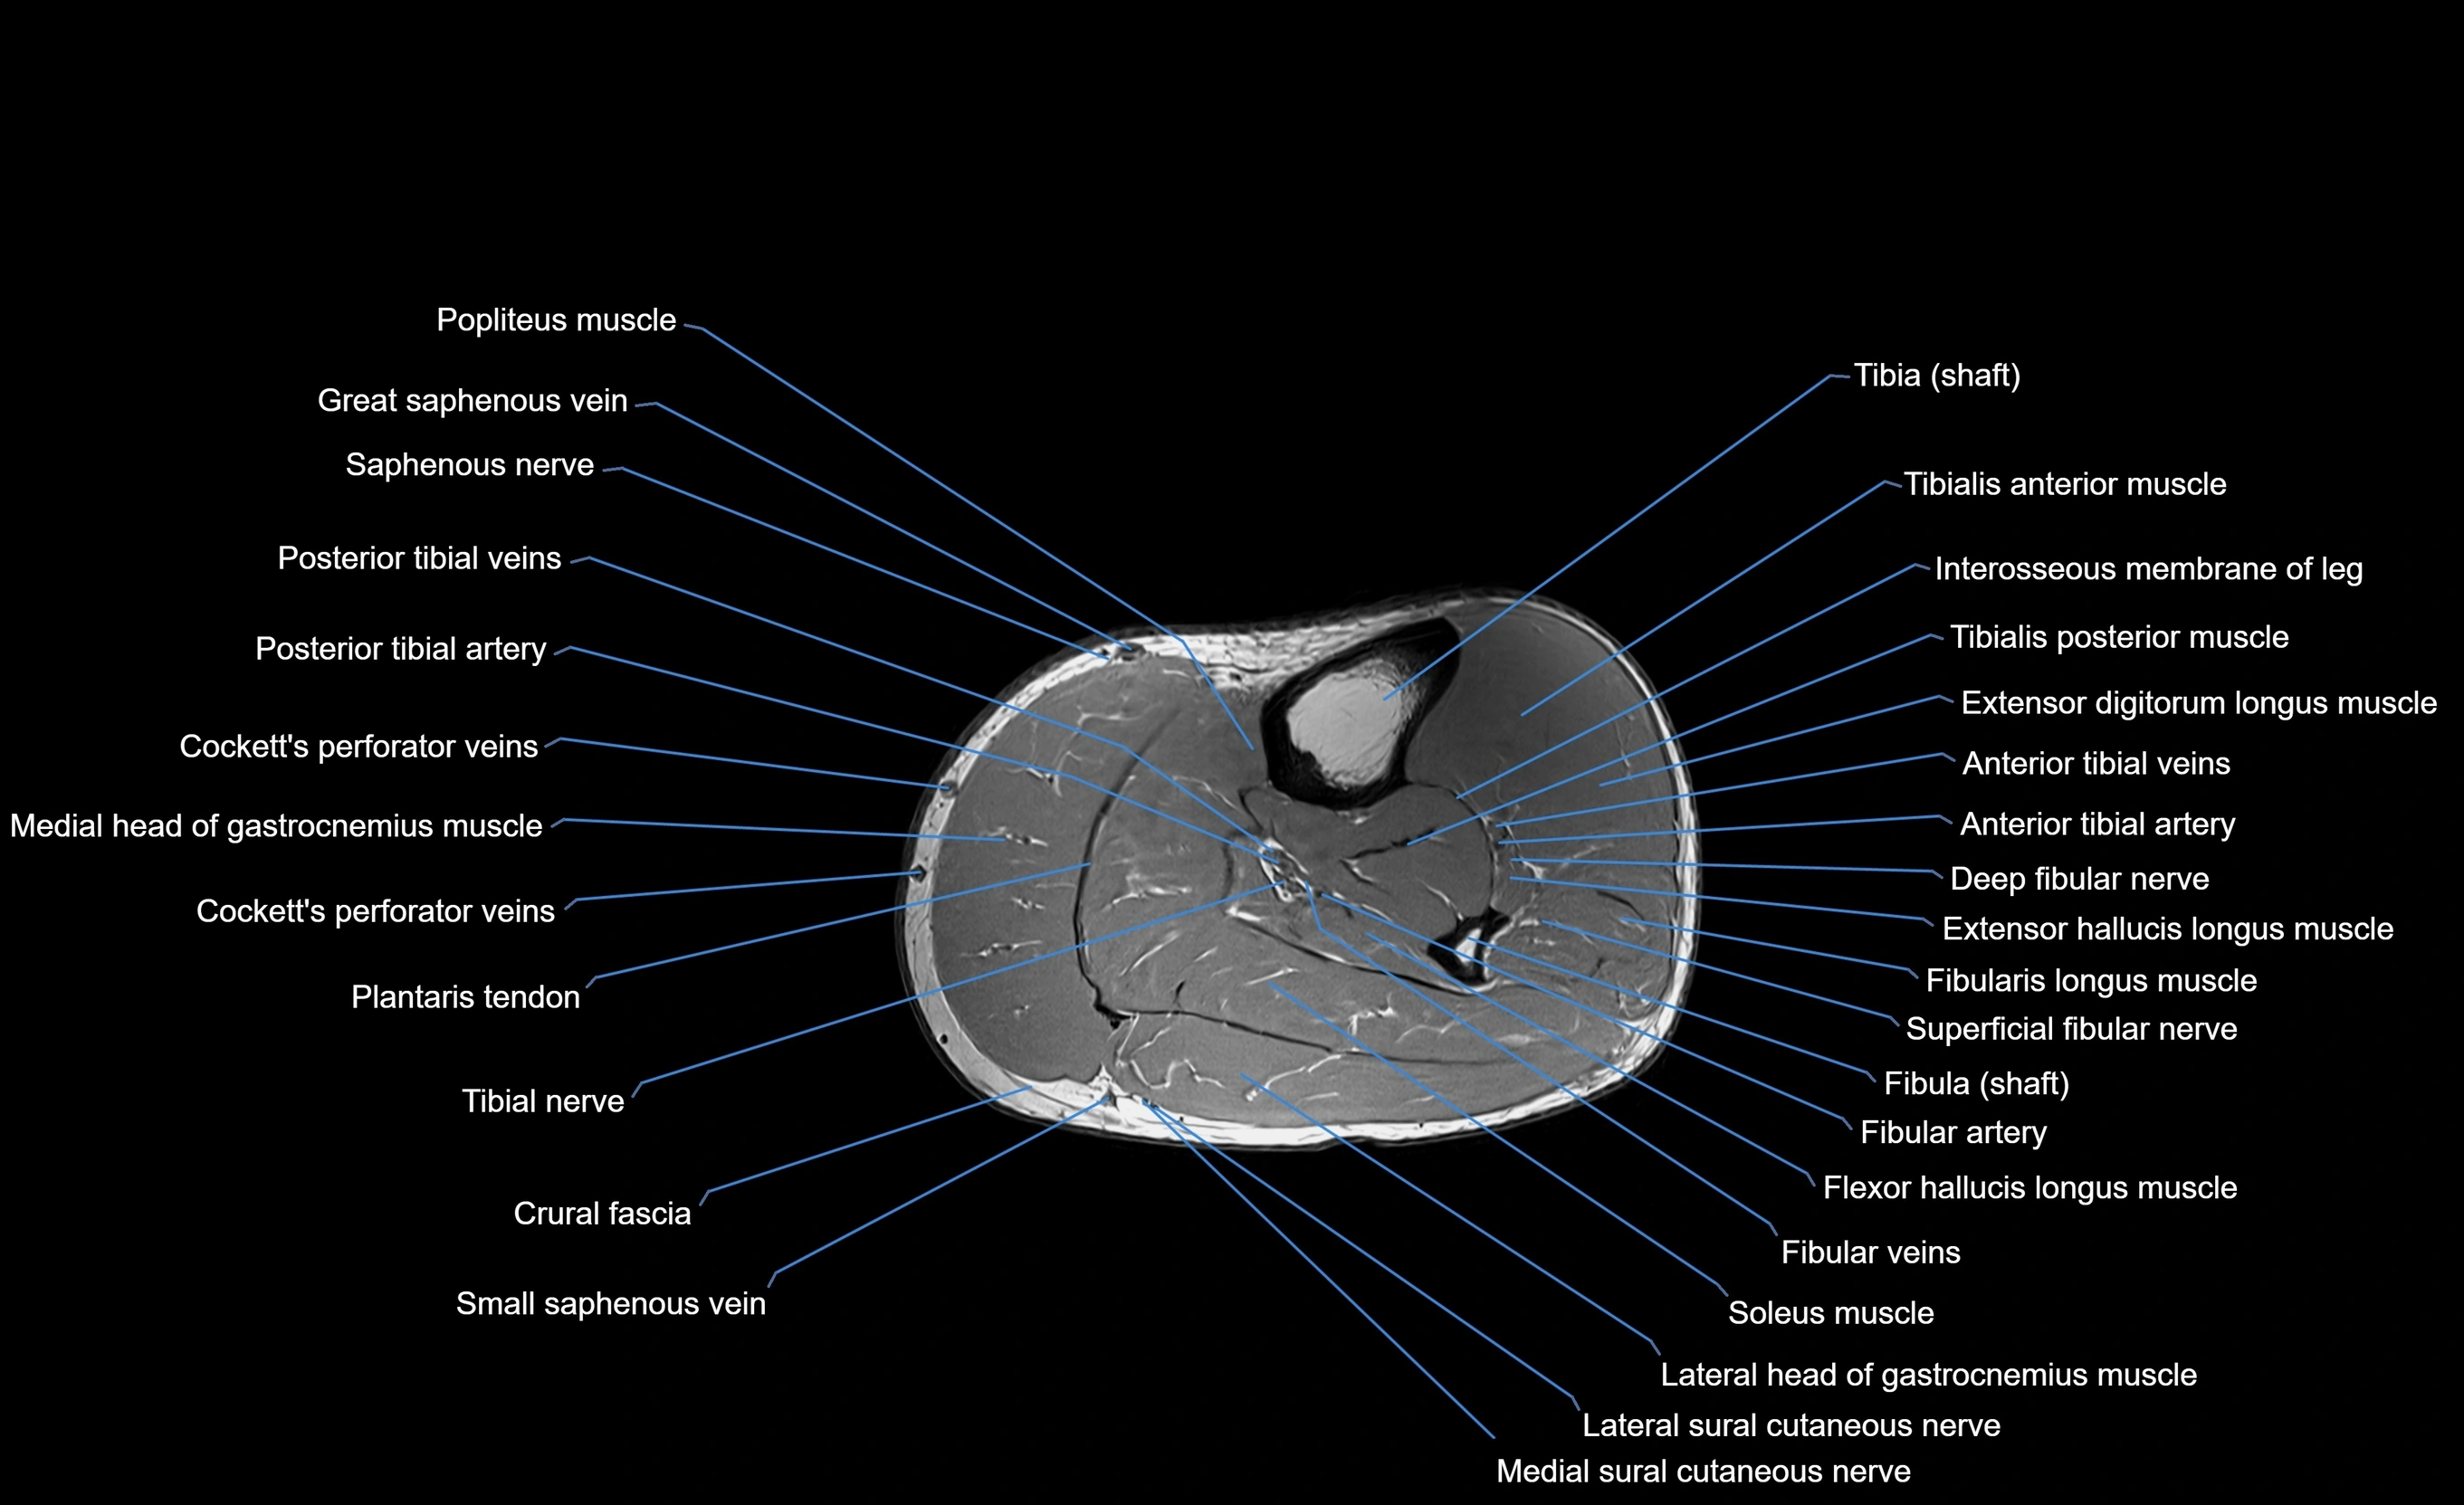

MRI image